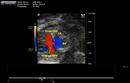

Caption: Color flow imaging of mutant 940-006-1 (E16.5) in frontal view showed aorta coming from RV, pulmonary artery sitting over the ventricular septum, which indicated DORV (Taussing-Bing type) also associated with two VSDs (inlet and muscular)

Click thumbnail to play movie. (details)

Represented Alleles:

b2b940Clo, Mutant line 940; Bench to Bassinet Program (B2B/CvDC), mutation 940 Cecilia Lo

Copyright: This image is from the Laboratory of Dr. Cecilia Lo, a member of the Cardiovascular Development Consortium (CvDC), Bench to Bassinet (B2B) program of the National Heart Lung and Blood Institute (NHLBI), and is displayed with the permission of the authors. J:175213

Caption: Color flow imaging of mutant 940-006-1 (E16.5) in frontal view showed aorta coming from RV, pulmonary artery sitting over the ventricular septum, which indicated DORV (Taussing-Bing type) also associated with two VSDs (inlet and muscular) (details)